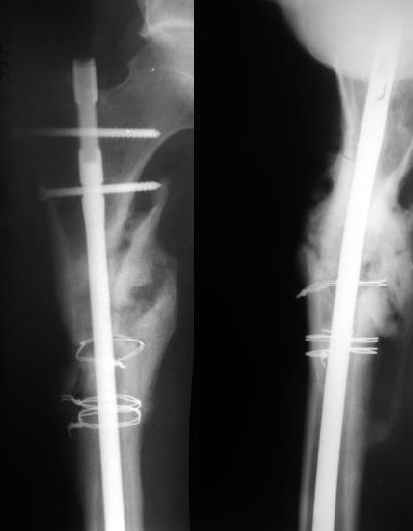

1) Мы бы не убирали проволоку, и вообще не вмешивались открыто на очаге - это ничего не даст, кроме ухудшения кровоснабжения концов отломков. Если просто закрыто перештифтовать при подобной картине, лучше с рассврливанием - это по нашему опыту дает сращение в 100%. В приложении пример - болезненное несращение более года, результат через полгода.

1

2

2)запирающие винты выглядят чрезмерно короткими. А им бы тут надо хорошо держаться за оба кортекса. Это в проксимальном отломке можно ввести было только динамический винт, или вообще винты не вводить.